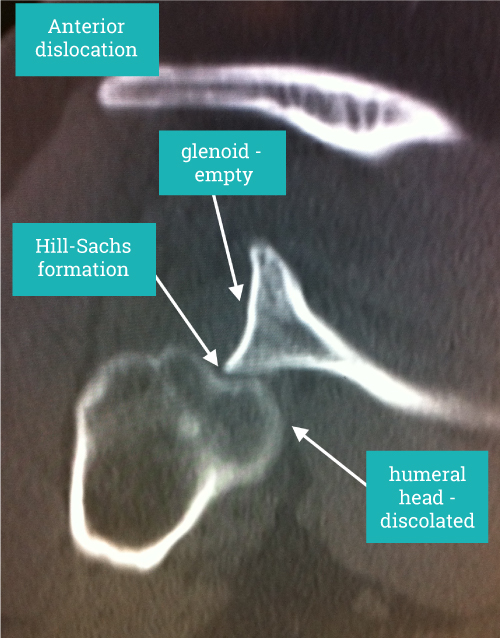

Hill Sachs Lesion

It describes the bone impaction caused by the humeral head sitting on the sharp angle at the front of the shoulder when it dislocates. Of itself it causes no long-term symptoms but can result in instability becoming persistent in the shoulder.

A symptomatic Hill-Sachs lesion is one that causes the shoulder to dislocate and surgery is based around preventing further dislocation either by addressing the primary cause at the front of the shoulder or in unusual cases addressing the Hill-Sachs lesion itself.